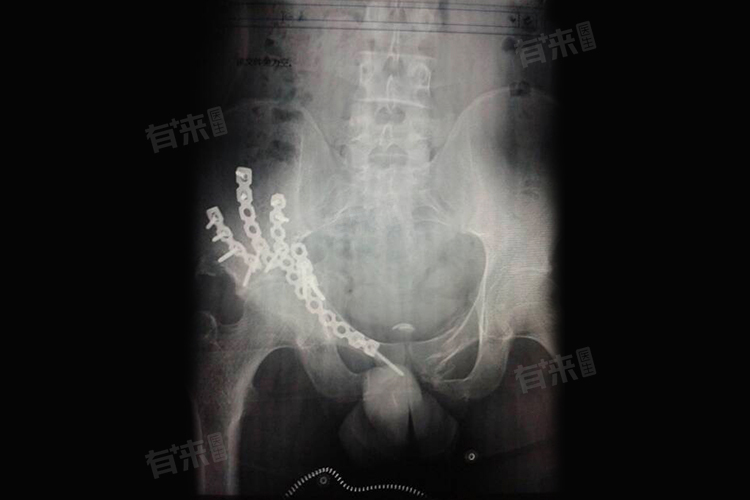

- 骨折打钢板手术过程中,需对患者进行充分的麻醉,并在麻醉生效后摆好适当的体位,进行严格的无菌消毒。随后,医生使用特殊的手术入路,迅速暴露骨折部位,进行解剖复位,并清理骨折断端。在直视下,骨折部位得到精确的复位,然后使用克氏针等方式进行临时固定。随后医生会根据骨折部位的具体情况,选择适合的钢板进行塑形,放置在骨折端,并使用螺钉逐步将钢板固定在此处。整个手术操作时间通常在1-2个小时,出血量相对较少,患者创伤也较小。

- 骨折打钢板手术的优势在于其固定效果良好,能够有效地将断裂的骨头固定连接在一起,维持骨折的解剖复位,防止骨折断端再受到剪切力或活动时导致骨折移位。这种牢固的钢板内固定有利于骨折端肌肉、软组织血运的保护,促进骨折端早期愈合,同时可以为骨折愈合修复创造有利的条件。钢板固定后可以早期进行功能锻炼,避免关节出现粘连、僵直,有助于关节功能的恢复。患者在术后可以早期进行功能康复,加强周围肌肉力量,防止肌肉萎缩。